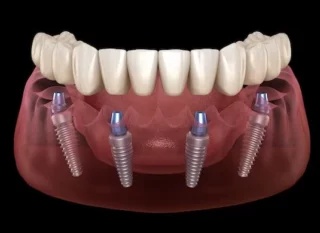

Az all-on-four, all-on-six technika lehetővé teszi egy teljesen fogatlan páciens számára is, hogy akár egy napon belül fogimplantátumon rögzített, teljesen stabil fogsorra cserélje korábbi kivehető protézisét.

A legtöbb esetben megoldást nyújt azoknak is, akiket korábban eltanácsoltak a fogimplantátumos beavatkozásoktól az előrehaladott csontleépülés miatt. Így ők is viszonylag csekély műtéti beavatkozás révén nyerhetik vissza magabiztos mosolyukat és teljes rágóképességüket. Bizonyos esetekben szükség lehet egyidejű, kiegészítő csontpótlásra is, kizárólag CT vizsgálatot követően lehet pontos tervet készíteni, a fogimplantátum beavatkozásokat elkezdeni.

Az eljárás lényege, hogy egy forradalmi újításként az állcsontok elülső, úgynevezett tömör csontos régiójába kerül beültetésre alul minimum 4, illetve felül minimálisan 6 darab fogimplantátum oly módon, hogy a hátsók egy bizonyos ferde szögben rögzülnek. Az esetek túlnyomó többségében még idős korban is található alkalmas terület a front régióban e beavatkozás elvégzésére. A fogimplantátumokhoz legtöbbször csavarozható módon tudjuk rögzíteni az új, teljesen fix fogsorokat, így akár egy napon belül a korábbi kivehető protézisek helyére esztétikus, funkcióstabil rögzített fogsor kerül. A fogsor rögzítésére szolgáló fogimplantátum beültetése esetén a gyógyulási idő 3-6 hónap, melynek leteltével van lehetőség a végleges, akár a legmagasabb esztétikájú cirkónium körhidak elkészítésére, a teljes fogsor rögzítésére.